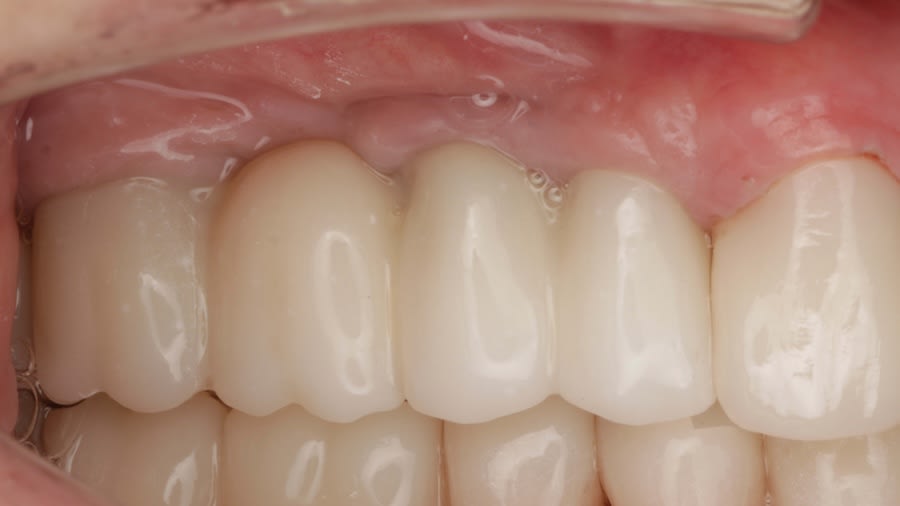

Case 1 (Figure 3 through Figure 24) depicts a 3-year follow-up of combined osseodensification sinus protocol IV in a severely resorbed maxillary ridge with ≤0.5 mm bone height in molar sites and horizontal deficiency at the first premolar site, using a two-stage approach for implant placement.